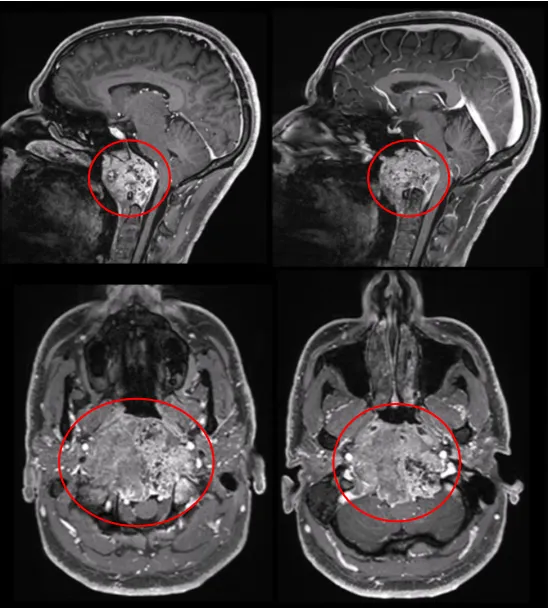

2.脊索瘤:脊索瘤起源于胚胎残留的脊索组织,从rathkes憩室扩展至斜坡,继续向下累及尾部的椎体。典型的斜坡脊索瘤的特点为居中线区的肿块,内见部分钙化,破坏斜坡骨质,并可见软组织肿块突入蝶窦或鼻咽。

点击阅读:切不干净,易复发?这个难缠的脑瘤手术“不基础”,术后放疗也“不基础”!